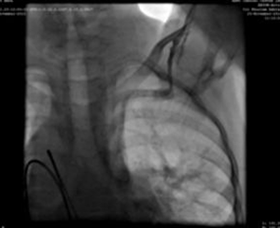

We used a 9F delivery sheath, which was advanced over and placed in the descending aorta over the super-stiff guidewire. A MemoPartTM cone shape PDA occluder 14/12 mm, was attached to the delivery cable and progressed across the delivery sheath. The placement of the occlude was proper with no residual flow.